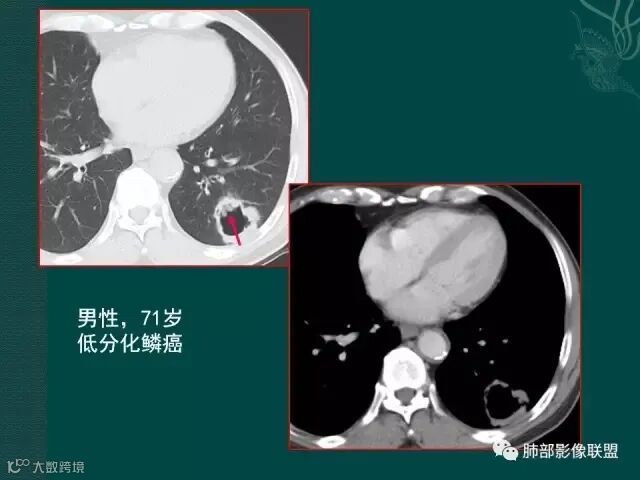

厚壁,大部分坏死,外缘较清晰,穿刺时千万不要穿坏死区;

鳞癌破坏力在所有类型肺癌中,都是最强的,所以出现坏死的几率特别是大片坏死的概率,是远远高于腺癌。